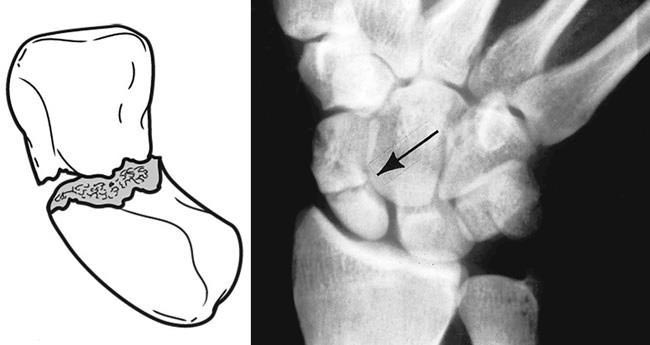

舟骨骨折是常被忽視的受傷,因為單靠X光未能準確排除,一定要配合醫生的臨床檢查和特別角度的X光及磁力共振才可判斷。舟骨骨折最可怕的併發症是當骨折被忽略和處理不當,會導致舟骨骨枯,最終影響手腕的功能、活動能力以及加速退化。

由於舟骨的血液循環特別慢,愈合時間比其他骨折更費時,需要2至3個月。

傳統方法是以石膏固定拇指及手腕,需時2至3個月。石膏雖可以固定使骨折愈合,但經過長時間的固定,手腕的活動範圍及功能都會受限制,隨後需要配合4至6個星期的物理治療復康。